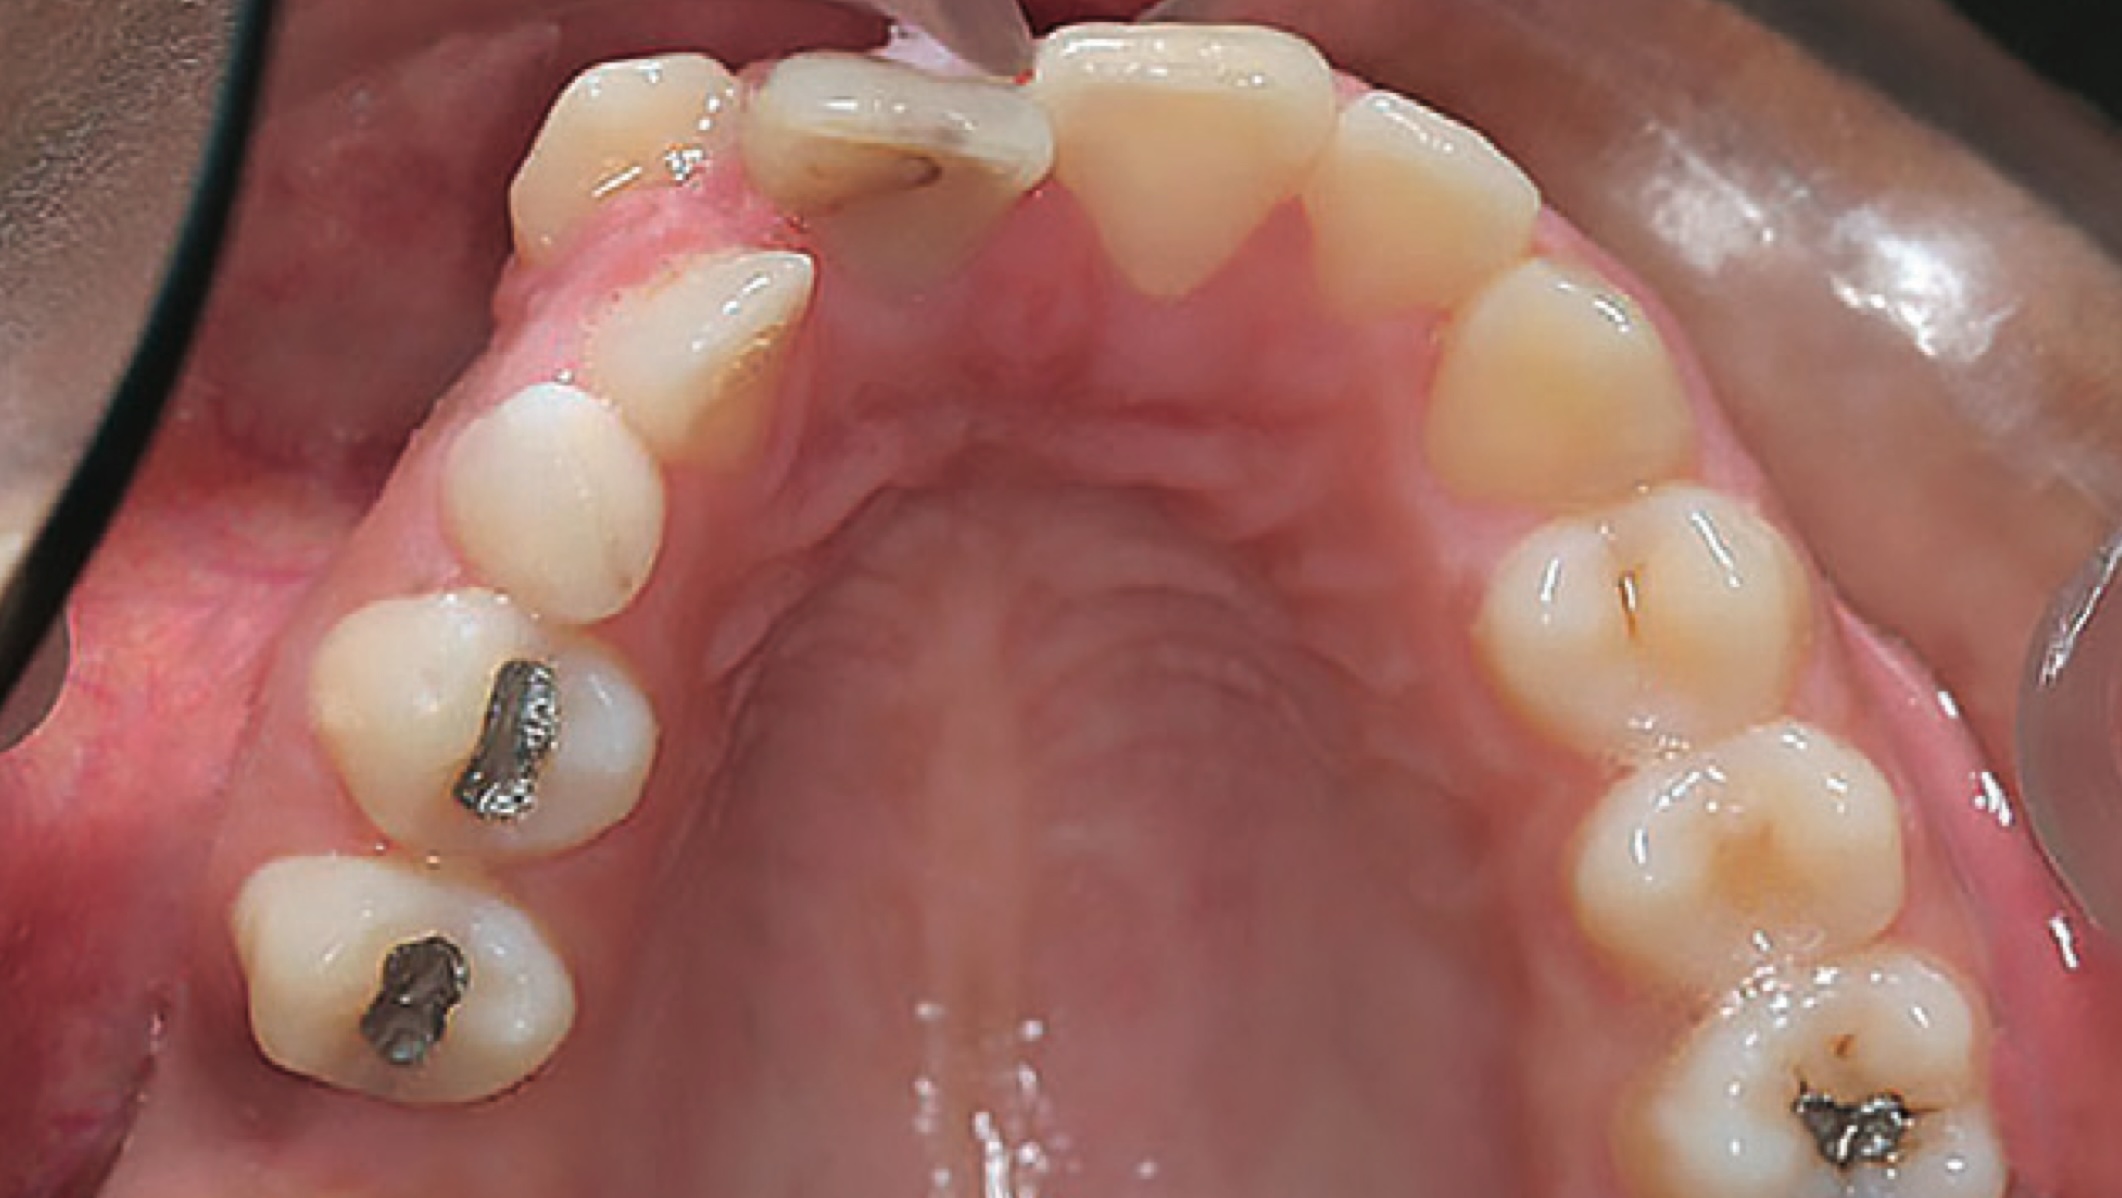

El siguiente reporte de casos llamado Treatment of a Patient with Apparent Primary Failure of Eruption Using a Modified Hyrax Expander and Miniplate Anchorage y publicado en el JCO, demuestra el tratamiento ortodóncico de un paciente que presentaba signos de fracaso primario de la erupción pero que dio negativo en las pruebas de mutaciones PTH1R ( receptor de hormona paratiroidea 1) .

El fracaso de la erupción es un trastorno espontáneo o hereditario que se manifiesta típicamente como una mordida abierta posterior grave y es difícil de tratar ortodóncicamente. El fracaso mecánico de la erupción está causado por una obstrucción como un quiste, presión lateral de la lengua, apiñamiento, impactación o anquilosis y puede resolverse eliminando la obstrucción. Los trastornos de la erupción de origen genético incluyen el fallo primario de la erupción, la displasia cleidocraneal, el síndrome de Hunter y la osteopetrosis.